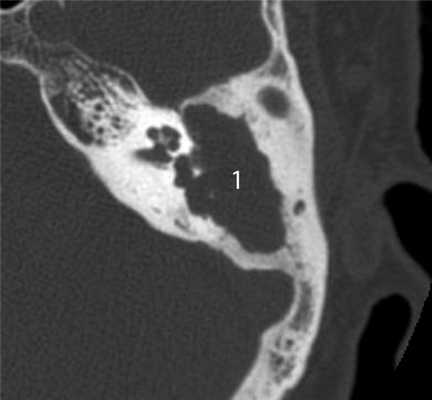

Главными отличительными признаками костной деструкции опухолевого генеза являются беспорядочность и широкая распространенность (рис. 4). Рисунок 4. Лангергансоклеточный гистиоцитоз. Аксиальная проекция правой височной кости. Распространенные беспорядочные деструктивные изменения остеолитического характера (1) в пирамиде и сосцевидном отростке. Мягкотканное образование (2) выполняет барабанную полость, обтурирует наружный слуховой проход. Участки костной деструкции могут быть выявлены на КТ в сосцевидном отростке, наружном слуховом проходе, в стенках барабанной полости и антрума, в капсуле лабиринта, в пирамиде височной кости и за ее пределами в костях основания и свода черепа [2, 4, 5]. Чем раньше обследуется ребенок с опухолью среднего уха, тем менее распространена деструкция в височной кости. Самые ранние стадии опухолевого процесса характеризуются ее отсутствием, что крайне затрудняет установление диагноза.

Другой отличительной особенностью деструкции при опухолях является литический характер, проявляющийся наличием в височной кости дефектов различной величины, значительным снижением плотности костной ткани в сочетании с неровностью и нечеткостью ее краев без явлений склероза (см. рис. 4).